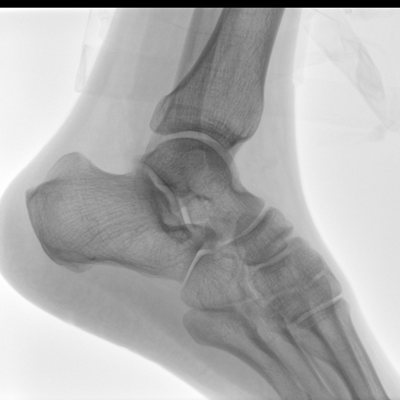

大尺寸液晶顯示器,圖像顯示清晰細膩;顯示器可大角度旋轉,滿足臨床多角度觀察圖像的需要。